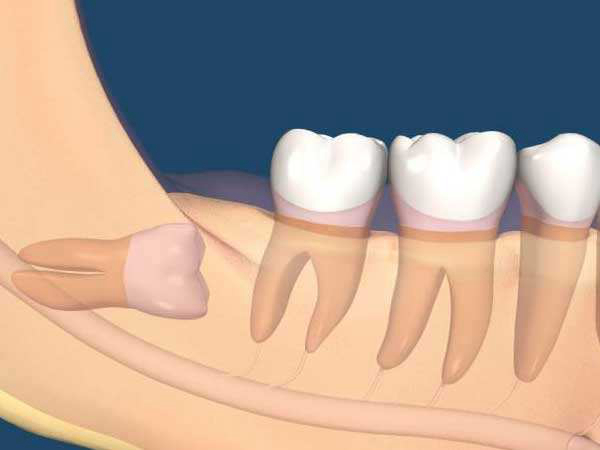

假如智齿位置比较奇怪,最终食物可能会在牙齿间残留,而智齿过于隐蔽,很容易会长出蛀牙,假如不及时拔掉可能会影响到其他的牙齿。

假如长智齿的时候相当疼痛,甚至于难以忍受严重影响正常生活,那么智齿应该拔掉,这样才能避免情况加剧,拔掉才是比较明确的选择。